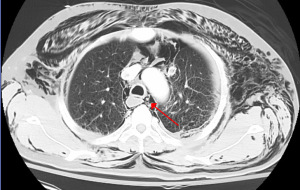

As standard for pneumomediastinum, one would begin with CXR. If CXR is non-diagnostic, but suspicion remains high for pneumomediastinum, CT chest may be obtained (Figure 1) (7,25).

Further diagnostic maneuvers, such as bronchoscopy, laryngoscopy, esophagoscopy, or esophagogram need not be routinely performed, but selectively performed based on clinical suspicion (3,7,25). If clinical history suggests likely airway injury, as in the case of traumatic injury, bronchoscopy should be performed. Clinical instability as defined by unstable vital signs, would also necessitate more aggressive workup, including repeat CT chest, bronchoscopy to rule out missed air leak and esophagram, and/or esophagoscopy to rule out esophageal injury (7,9,10).